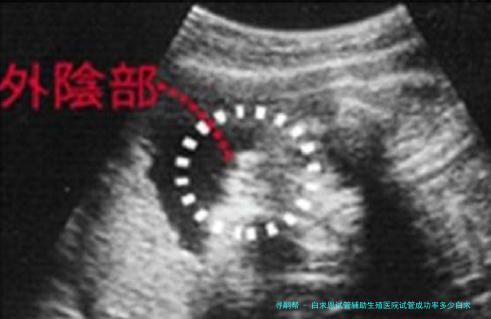

白求恩试管辅助生殖医院做试管婴儿成功率一览